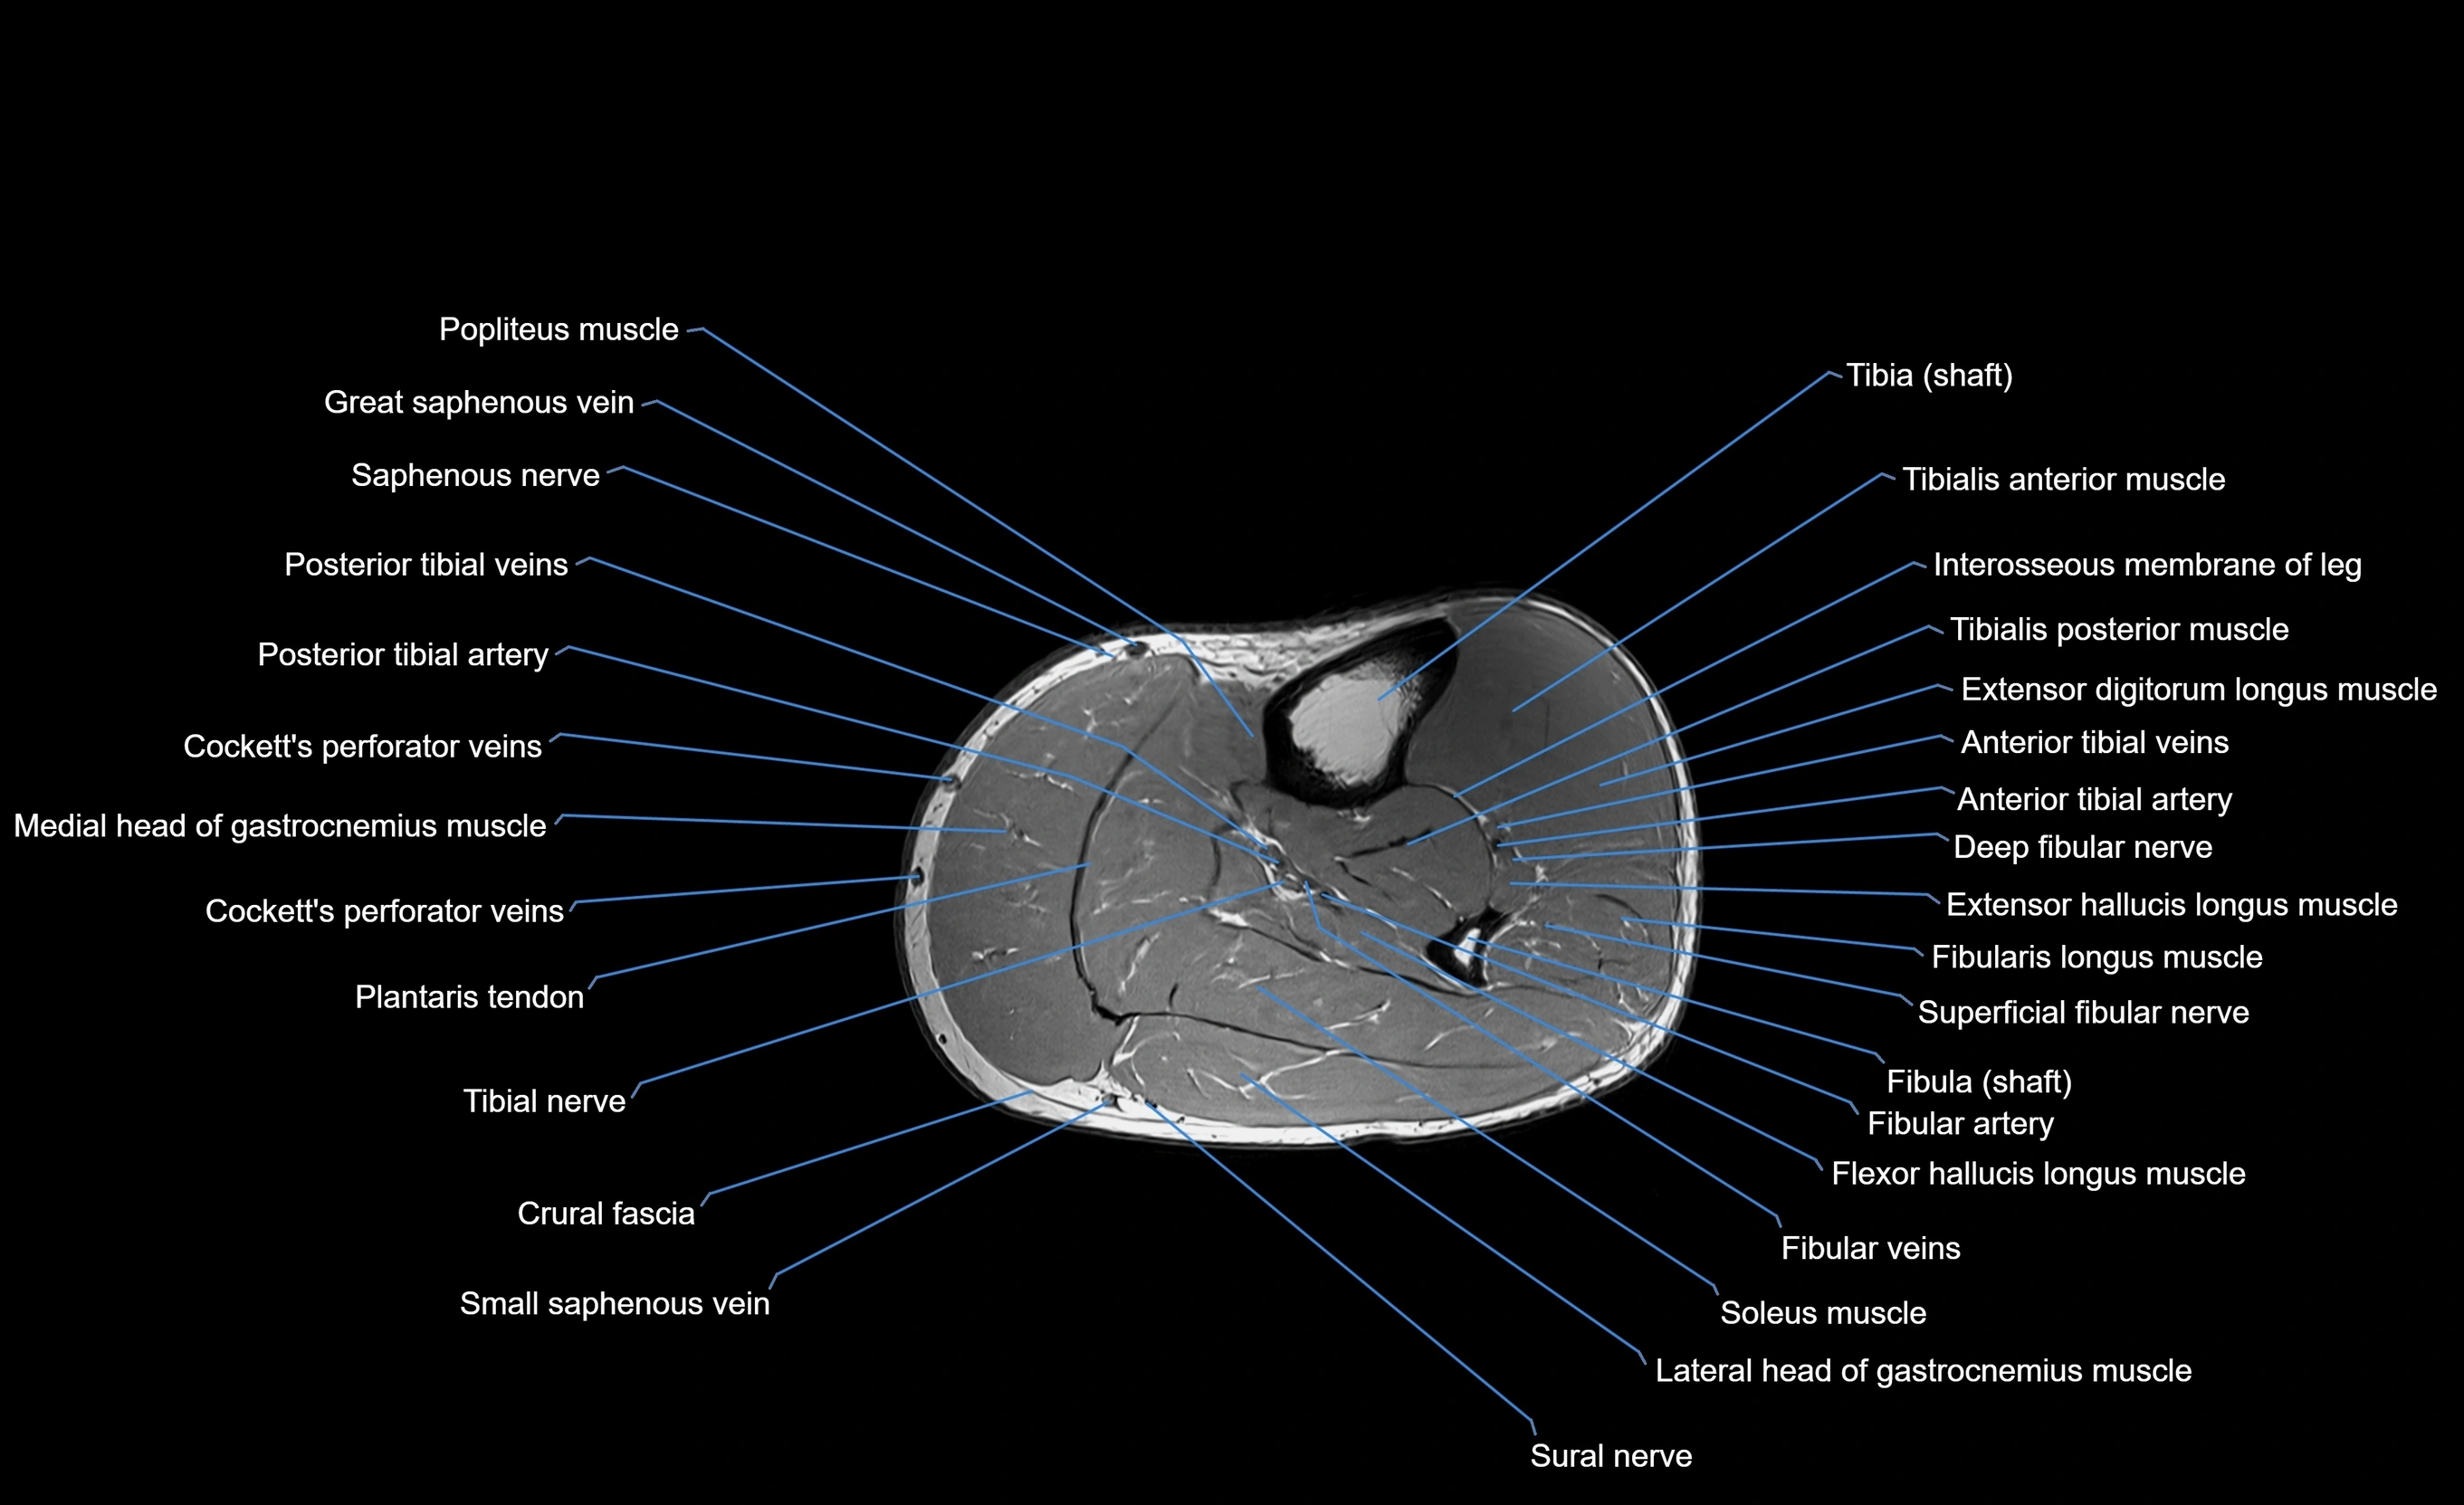

MRI image